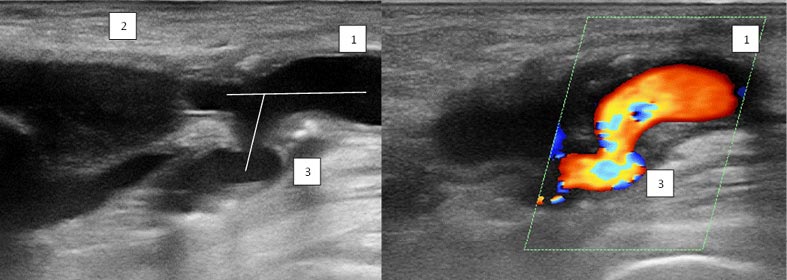

Результаты. При дуплексном сканировании артерий нижних конечностей обращало на себя внимание изменение угла отхождения ГАБ у пациентов после проведённого оперативного лечения по сравнению со здоровыми добровольцами. В норме угол отхождения ГАБ относительно общей бедренной артерии во всех случаях не превышал 30°: в 90% случаев (27 пациентов) он соответствовал 20°, в 10% (3 пациента) — 30°. RI составил 1,0±0,2 (рис. 1).

Рис. 1. Дуплексная сканограмма области бифуркации общей бедренной артерии у здорового добровольца: 1 — общая бедренная артерия; 2 — поверхностная бедренная артерия; 3 — глубокая бедренная артерия (угол её отхождения 20°)